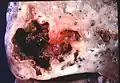

Lung abscess is a type of liquefactive necrosis of the lung tissue and formation of cavities (more than 2 cm)[1] containing necrotic debris or fluid caused by microbial infection.